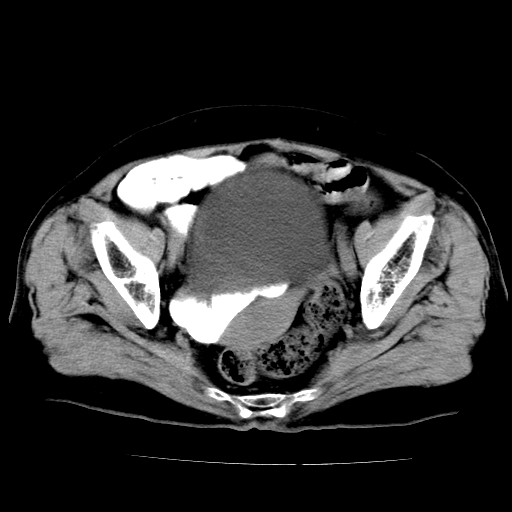

女,73岁,阴道流血一周。

宫颈不规则增大;结合临床考虑宫颈癌。建议作mri检查

1\\老年妇女突发阴道流血,常见病考虑宫颈癌.本病例宫颈部显示形态不规则,密度欠均匀,支持考虑宫 颈癌,建议mri 或阴道超声坚持

2\\但是盆腔两侧尚未见到明显肿大淋巴结等转移征象

宫颈不规则增大,左后方可见结节状突起.支持宫颈癌.

宫颈壁明显增厚,左侧为甚,宫颈癌待排,建议宫颈涂片细胞学检查。

宫颈不规则增大,周围脂肪间隙毛糙,结合临床考虑宫颈癌,盆腔内未见肿大淋巴结。